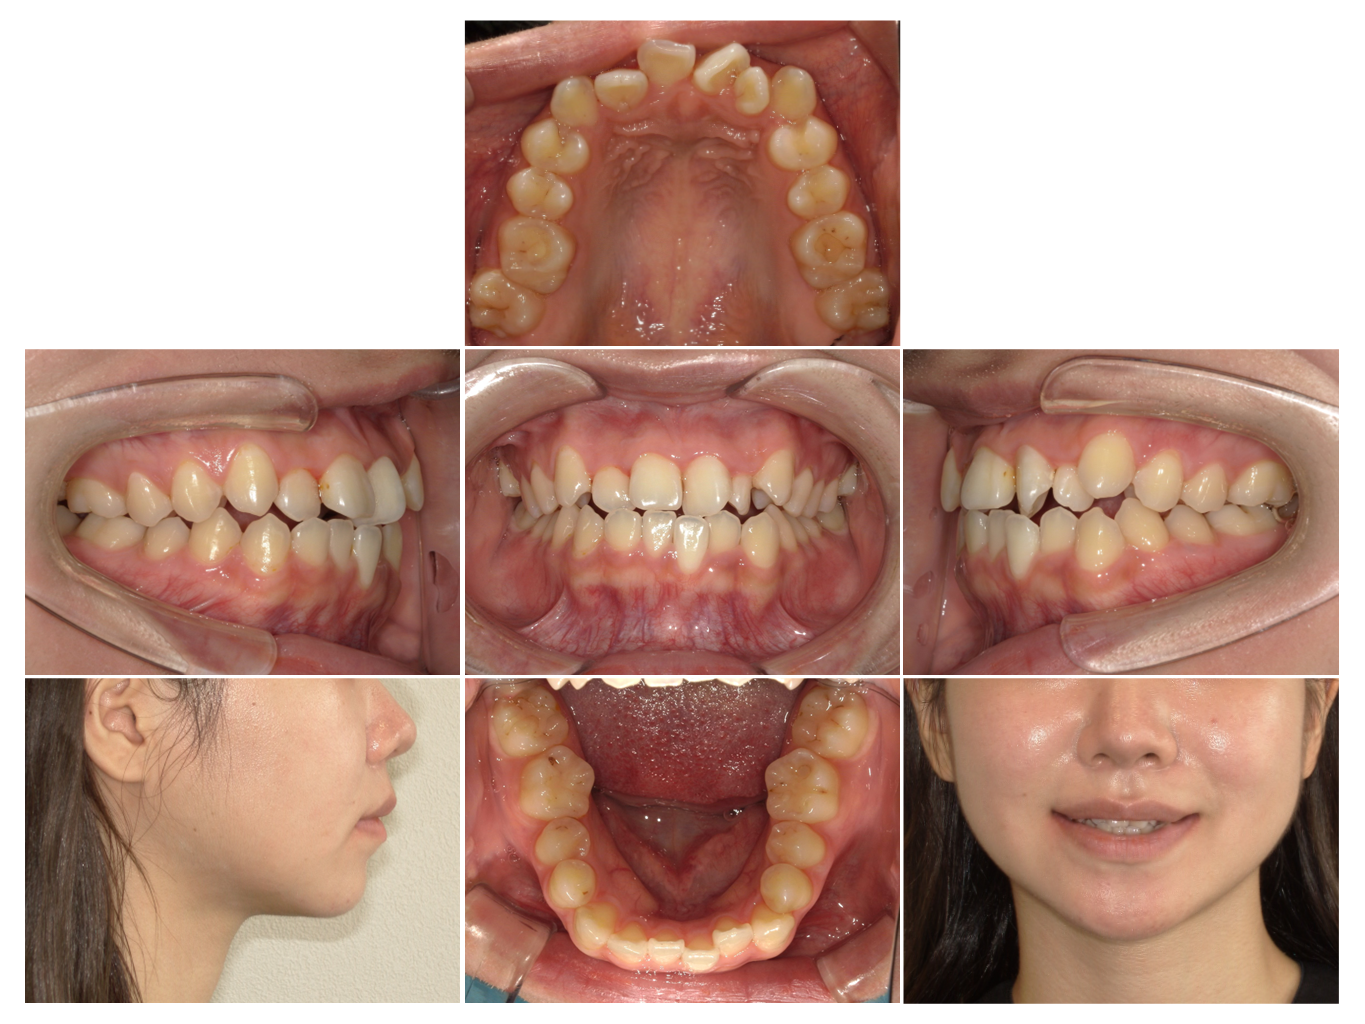

症例7

| 来院時の主訴 | 全体的なガタガタ |

| 医院での対応や適用装置 | マウスピース矯正装置を使用して主訴である |

| 通院期間 | 8ヶ月 |

| 通院回数 | 6回 |

| 治療費用総額 | 726,000円(税込) |

| リスクと副作用 | 矯正治療による歯の移動に伴う痛み、歯根吸収、虫歯 |